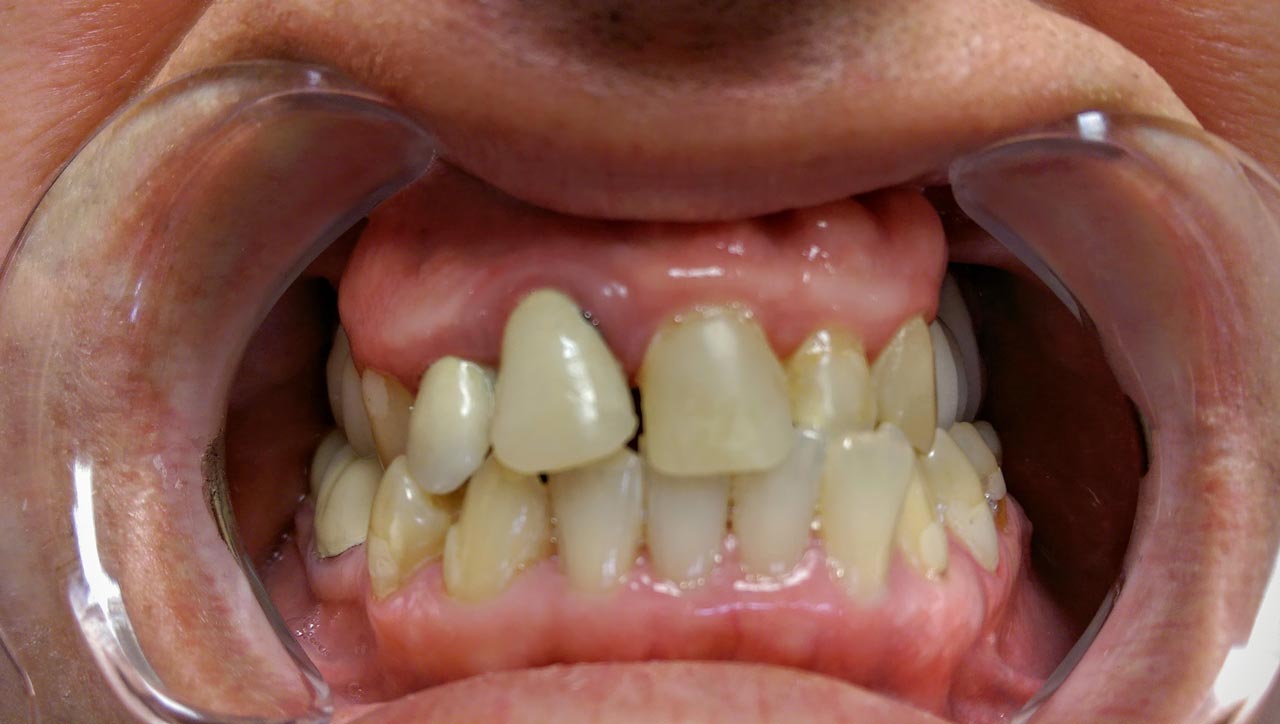

Teljes szájüregi rehabilitáció két lépésben

Ismét egy teljes szájüregi rehabilitáció két lépésben. Először az alsó fogak lettek kihúzva és azonnal implantálva, híddal ellátva, majd később a felső. IHDE svájci azonnal terhelhető implantátumok és cirkónium hidak. Dr. Kelemen Péter és a Symbion Fogtechnika közös munkája.